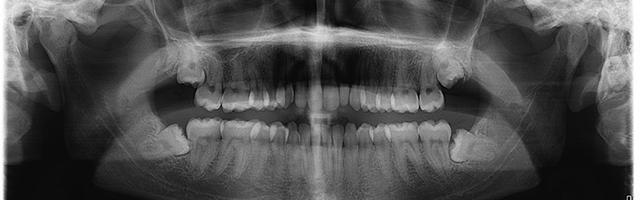

Dal punto di vista tecnico, l’estrazione dei denti del giudizio può richiedere un intervento più o meno invasivo a seconda della posizione del dente e dei suoi rapporti con le strutture anatomiche circostanti. In molti casi il terzo molare assume una posizione del tutto analoga a quella degli altri molari, e a essi parallela, e la sua estrazione generalmente non presenta grandi difficoltà, né richiede un approccio chirurgico.